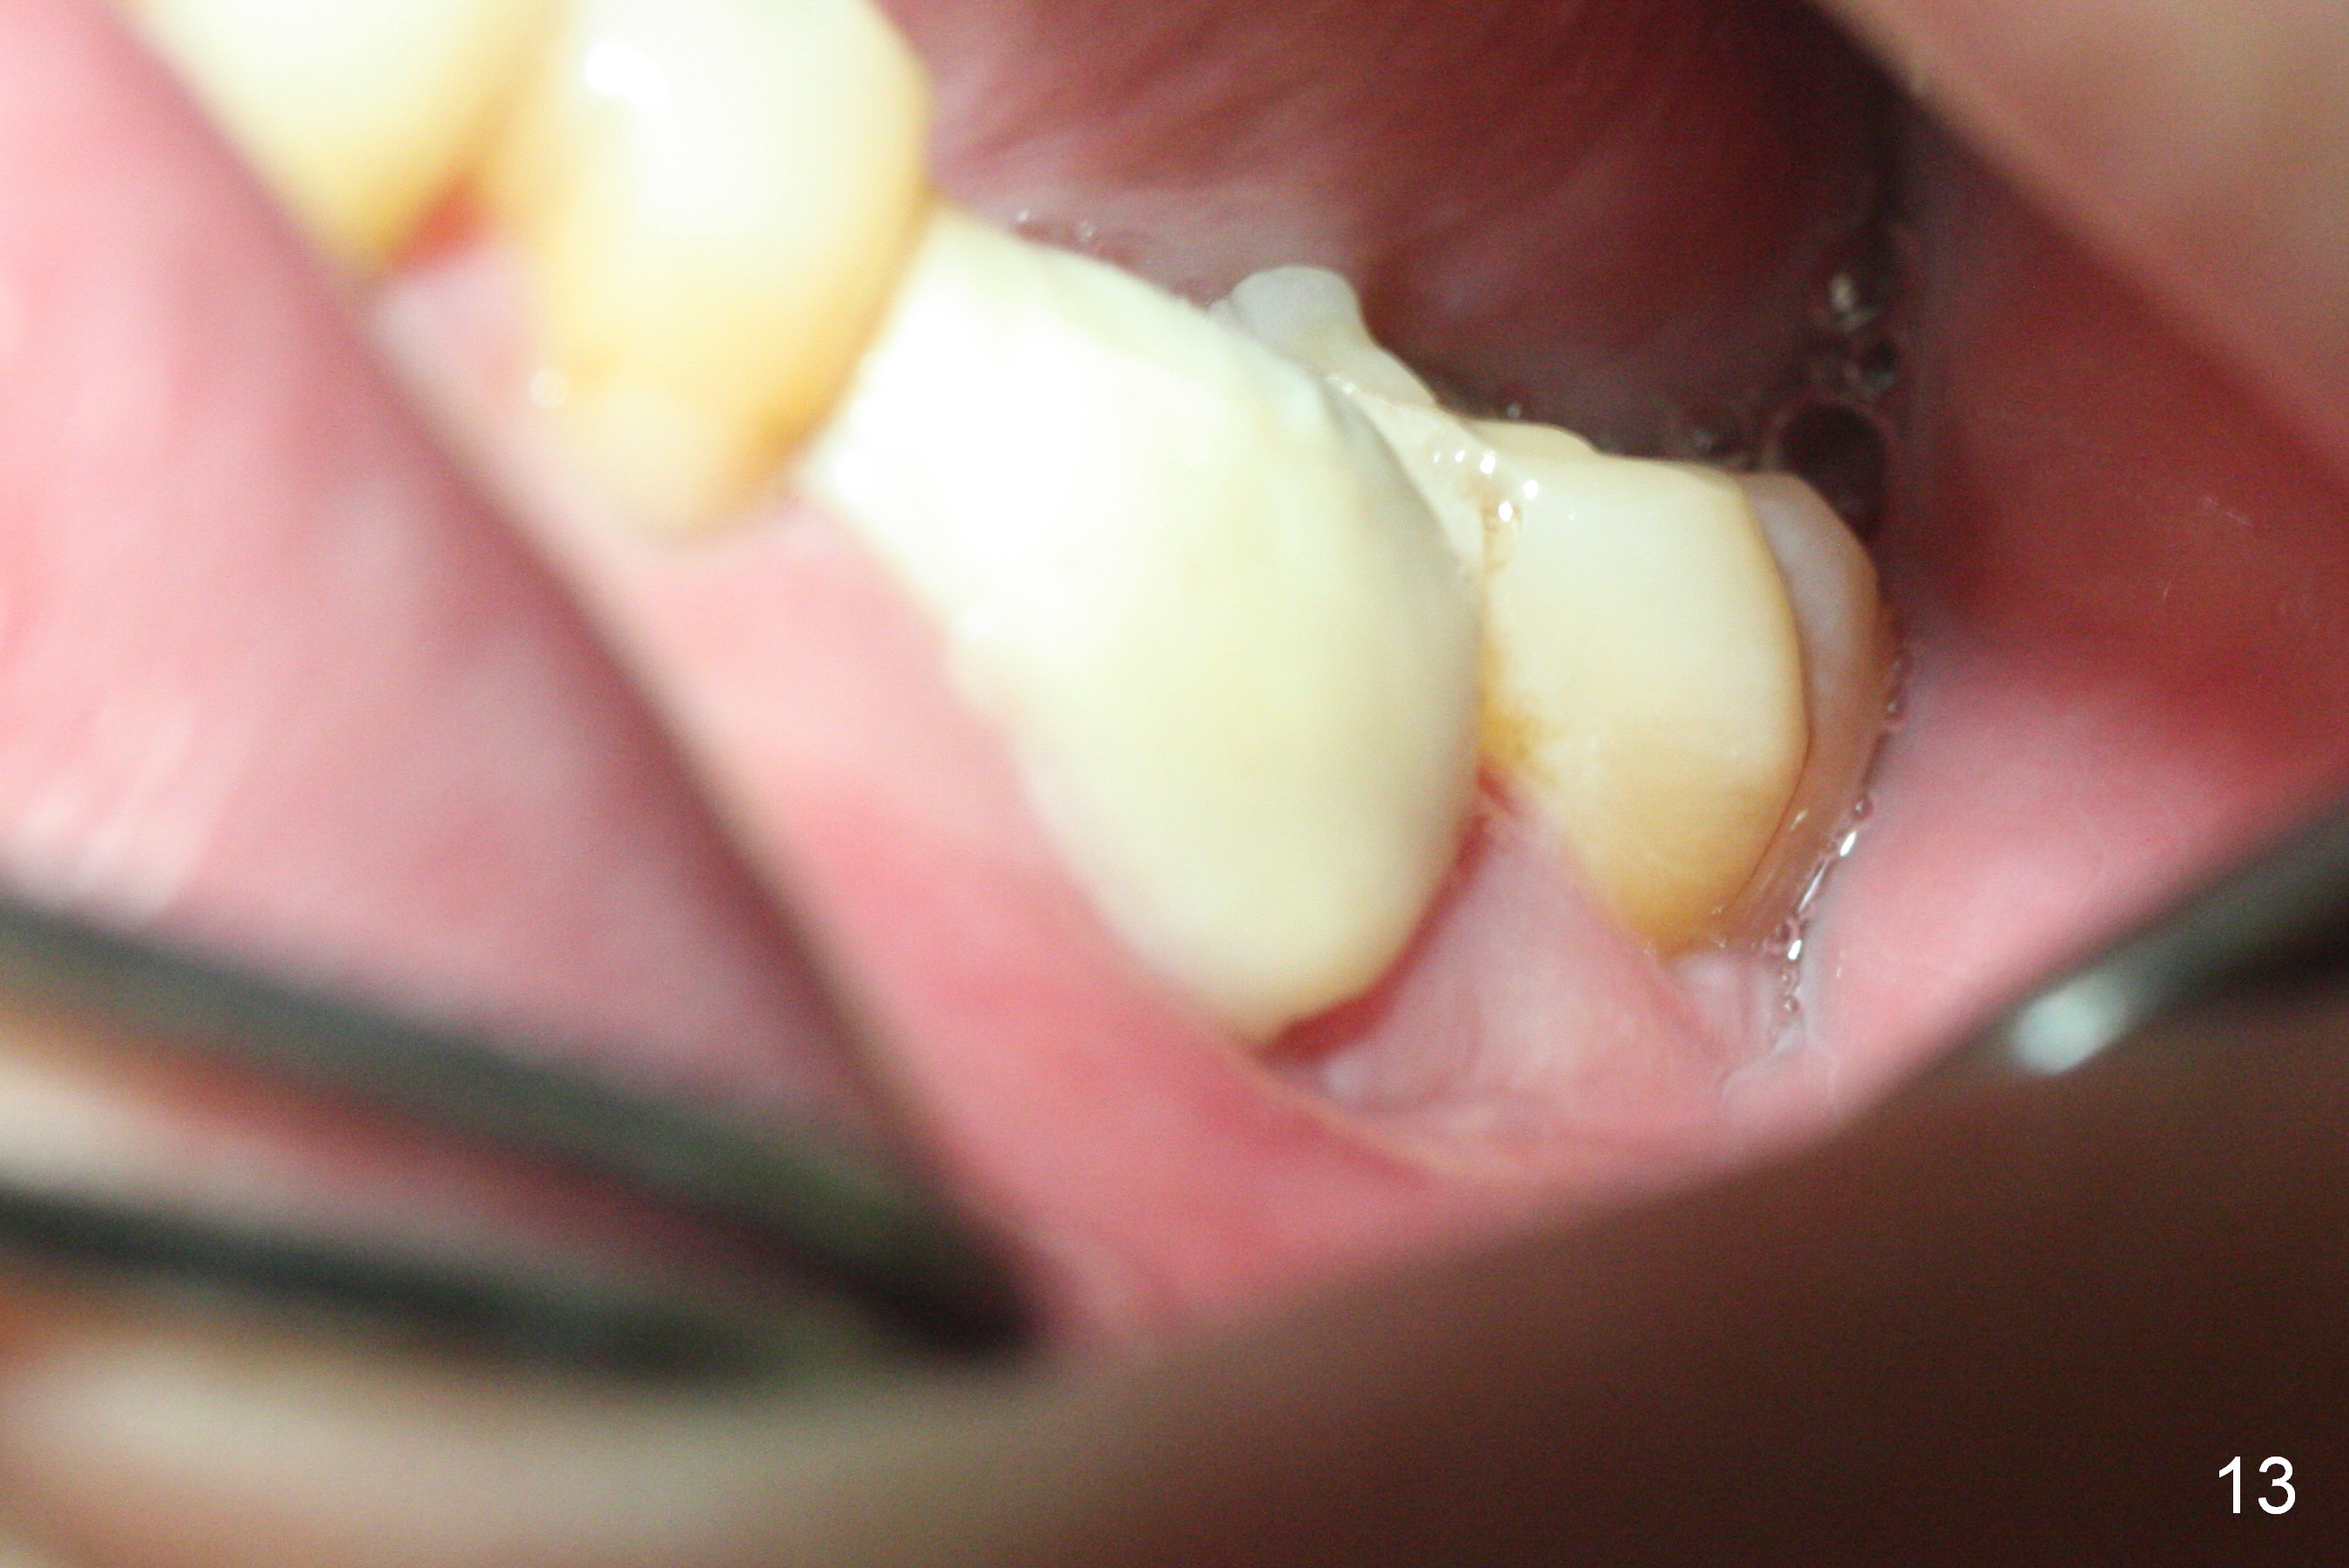

The asymptomatic tooth (#19) has a midbuccal fistula (Fig.1 <). The mesiobuccal pocket is 10 mm with purulent discharge from the sulcus (Fig.2,3). The mesiobuccal wall defect is confirmed when the tooth is extracted. Osteotomy is initiated lingually in the septum following septal crestoplasty (flattening) (Fig.4: using 1.6 mm drill for 9 mm). Since the lingual portion of the osteotomy is higher, it is difficult to use drill with stopper. For the narrow septum osteotomy, multiple drills are used sequentially (Fig.5 after 4.3 mm drill). A 4.5x11 mm dummy implant is placed (Fig.6) apparently too deep. When a 5x11 mm IBS implant is being placed, the depth is tightly controlled (Fig.7). The implant is apical to the lingual crest, whereas there is ~ 2 mm implant exposure buccally. That is, there is a large gap mesiobuccally (Fig.8), which is filled with .5-1.5 mm allograft (Fig.9 *). A 6.5x5.7(3) mm abutment (A) is placed and trimmed for an immediate provisional (Fig.10 P). The lacerated buccal gingiva is sutured as well as application of Perio Glue.